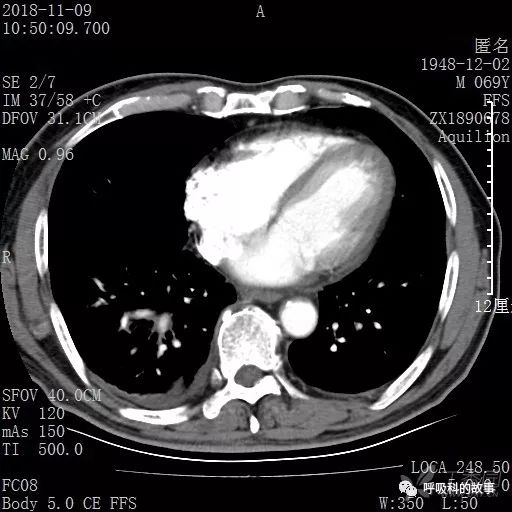

胸部增强CT示右肺门占位伴远端阻塞性肺炎,纵膈、右肺门、右侧颈根部、右侧腋下及肝门部肿大淋巴结。两侧胸腔少量积液。

肺窗CT